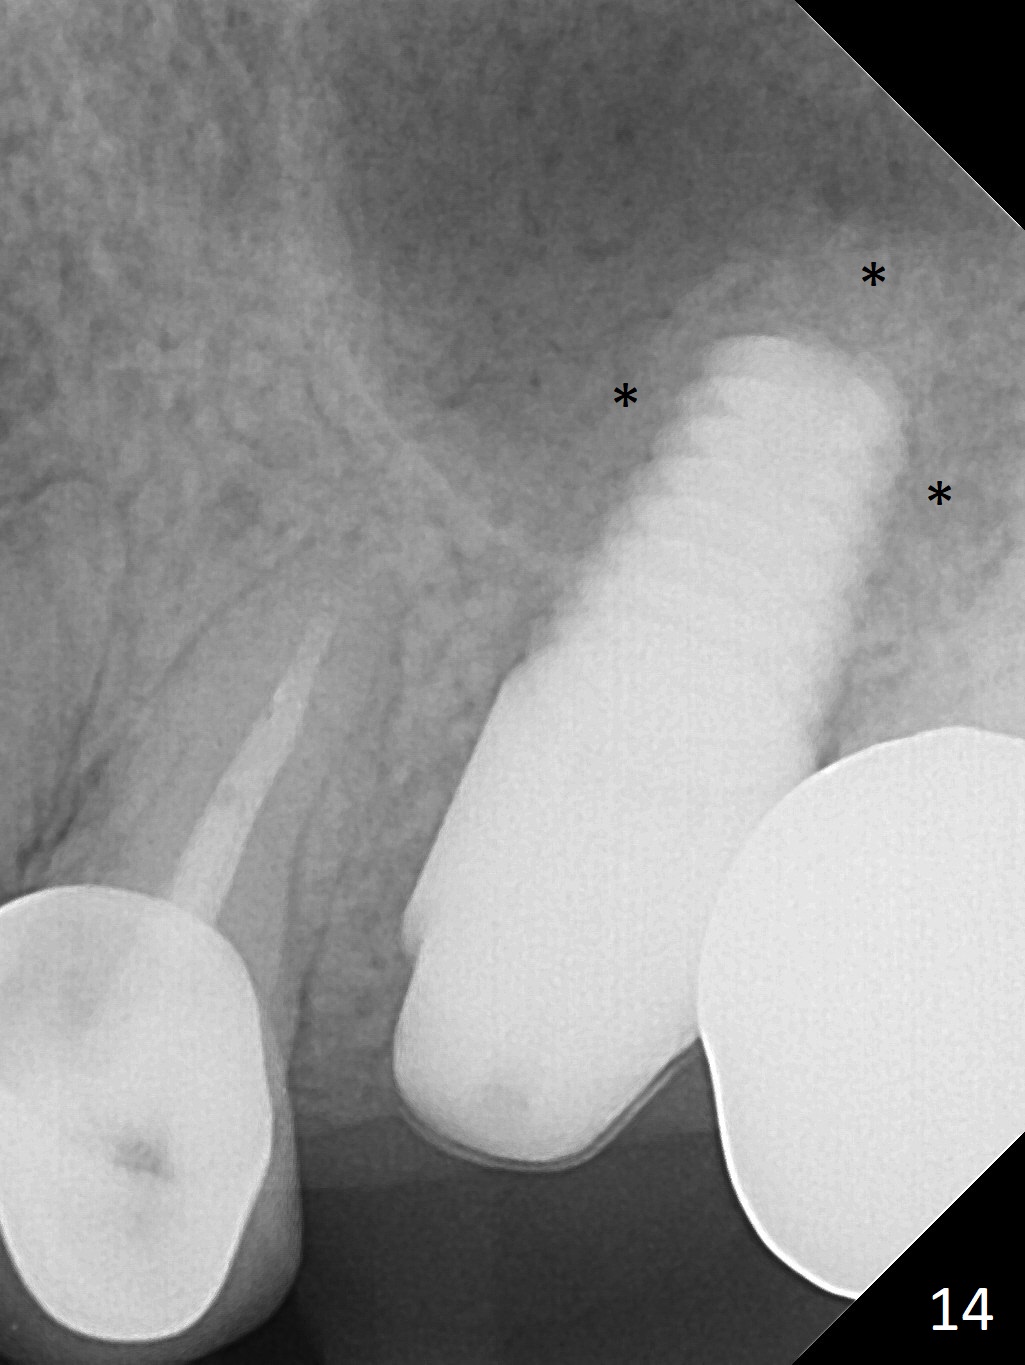

The patient is doing well 9 days postop.  The immediate provisional is loose and over-sized.  It is removed for trimming and reline; the socket and bone graft (Fig.8 *) are healing.  It appears that an angled abutment is required next time of provisional revision.  When an angled abutment is being placed 23 days postop (Fig.9), it appears to wiggle the implant due to its long leverage.  Instead a healing abutment is placed.  The implant is unstable 4.5 months postop with seemingly excessive bone-implant gap (Fig.10 <).  The 5.5x9 mm implant is removed.  A 5x17 mm tap is used to change the trajectory and sinus lift, followed by 6x17 one (Fig.11).  Finally a 6x14 mm tissue-level implant is placed with insertion torque > 50 Ncm (Fig.12; vs. <20 Ncm (Fig.7,10)) and improved trajectory.  An immediate provisional is fabricated to prevent the mesial drifting of the tooth #15 (Fig.13 P (*: occlusal clearance)).  By using the taps and placing the longer implant, the sinus lift is more obvious (compare Fig.10 and 12 (*)).  Sinus lift remains evident 3.5 months postop (Fig.14) with apparently osteointegration (Fig.15).